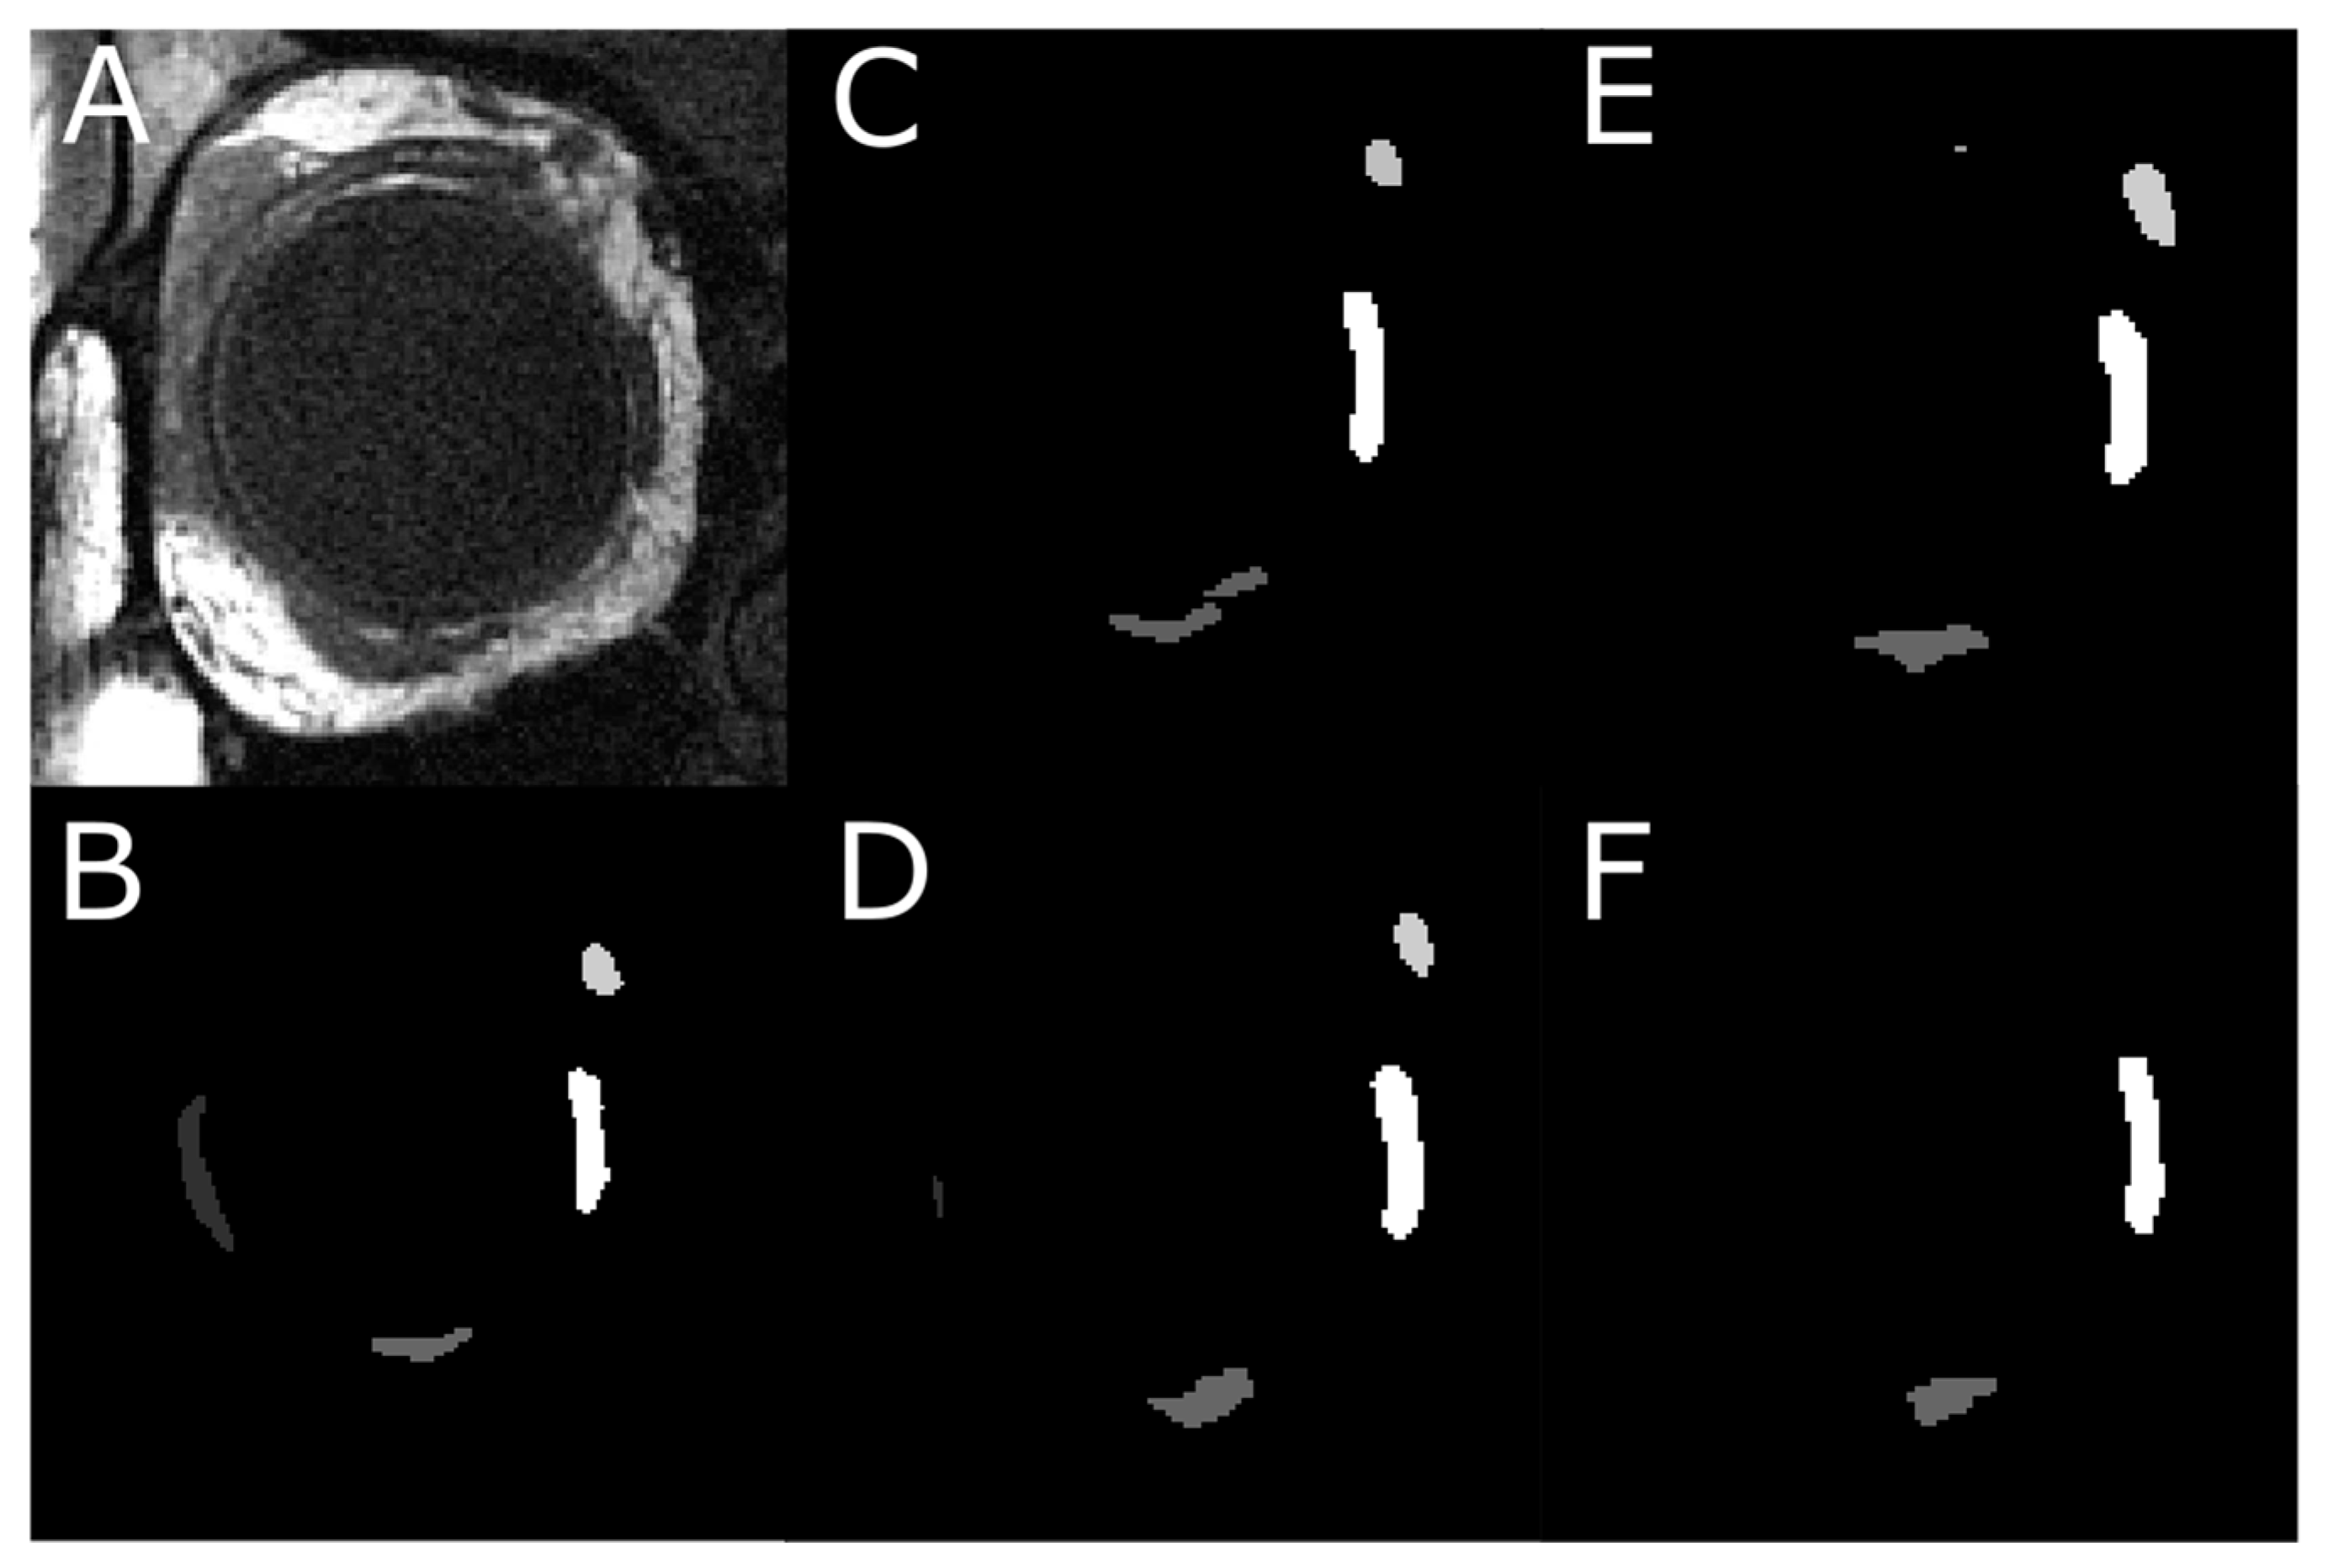

3.4. Analysis of T-2 Weighted MRI Images

3.5. Impact of MRI Slice Location on Segmentation Accuracy